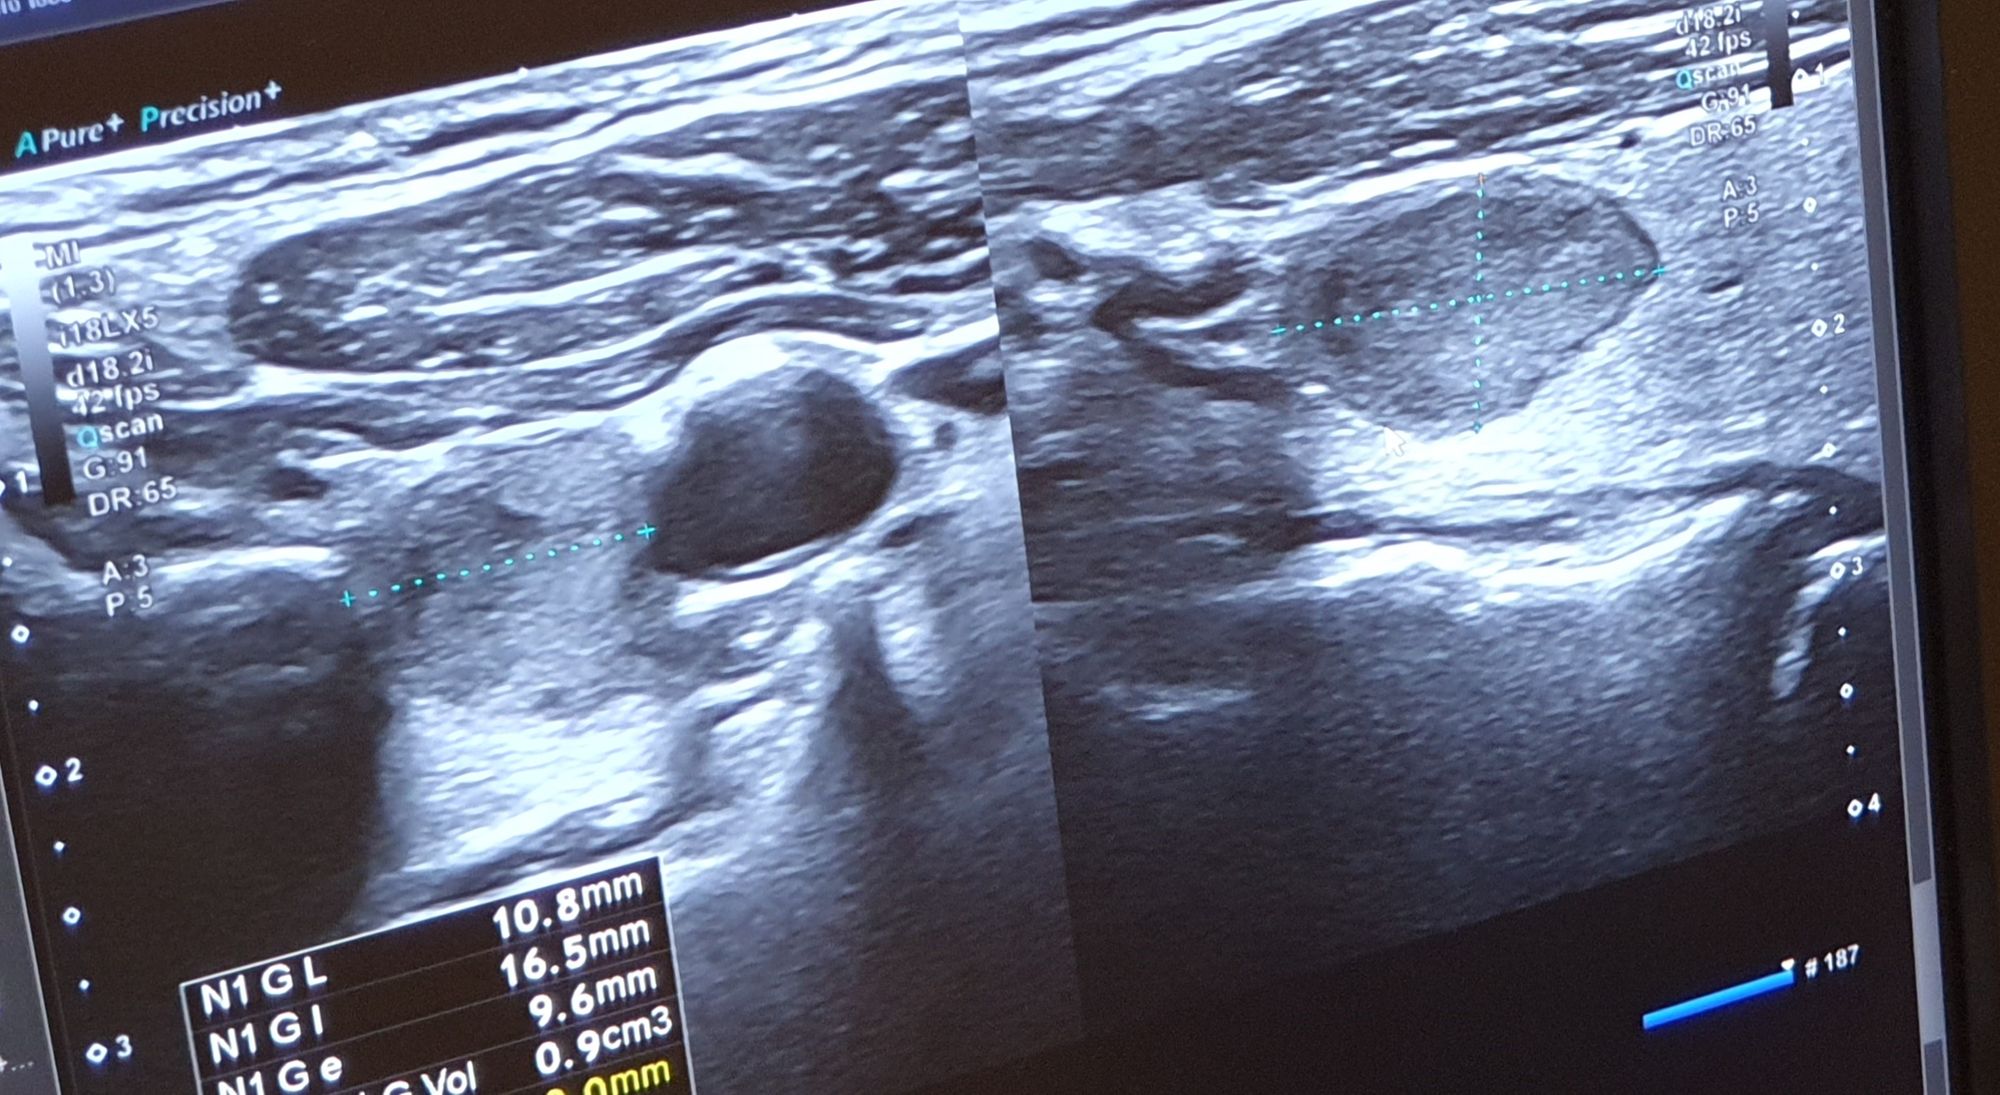

Le service Imagerie Médicale de l'Hôpital vous accueille au sein d'un nouveau bâtiment, Porte B du Bâtiment Buès, où est regroupé le pôle Scanner-IRM. Le Centre de la Femme, au rez-de-chaussée du Bâtiment Fouque, accueille l'imagerie dédiée à la femme (mammographie, échographie mammaire), alors que la radiologie, EOS, et les échographies sont réalisées au 1er étage du Bâtiment De Vernejoul.